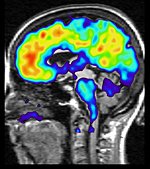

Foto: Andreas Andersson#175: Vad är frontallobsdemens?

Sänkt empati, personlighetsförändringar och hämningslöshet är utmärkande för personer som drabbats av frontallobsdemens. Det är ett samlingsnamn på flera neurodegenerativa sjukdomar som drabbar hjärnans främre delar. Hör professor Lars-Olof Wahlund berätta om riskfaktorer, symtom och hur forskarna försöker hitta behandling.